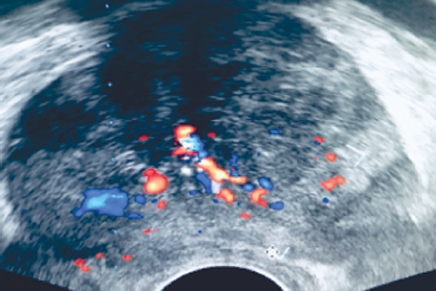

Figure 1 presents ultrasound imaging of the prostate gland with Doppler scanning of the vessels. This mode enables to map quite clearly the intraprostatic vessels, so damage should be avoided during the biopsy study. Figure 2 shows ultrasound imaging of the prostate gland, without the use of Doppler scanning of the vessels, which practically does not enable the determination of their distribution in the prostate, which increases the probability of their damage when obtaining a biopsy material.

Fig. 1. Ultrasound imaging of the prostate with Doppler control

Рис. 1. Ультразвуковая визуализация предстательной железы с доплеровским контролем